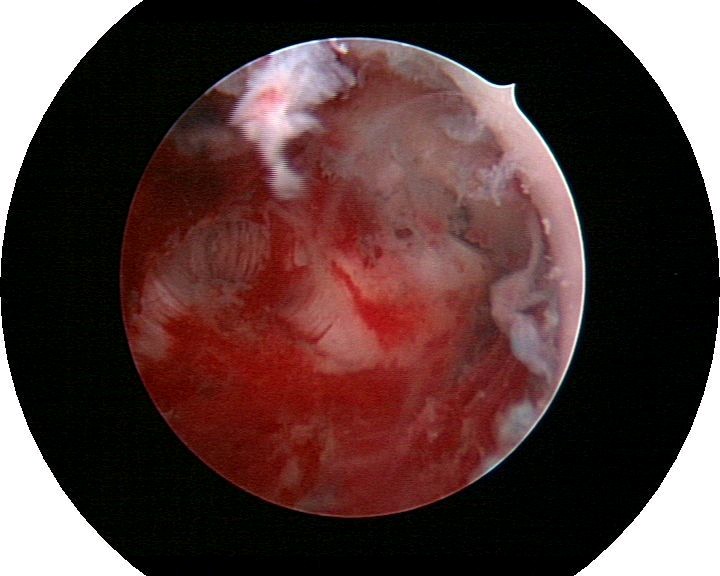

患者35岁,G4P0,2011年4月因继发不孕、月经减少2年,行宫腔镜探查,发现宫腔广泛重度粘连,单极电切分粘,恢复宫腔形态,显露双侧输卵管开口,放置节育环一个,术后月经恢复正常。2011年9月行宫腔镜二探并取环,O型环部分嵌顿,分离残留粘连,宫腔形态正常,双侧输卵管开口可见,同时行腹腔镜下左侧卵巢囊肿剥除术,术中通液双侧输卵管通畅。术后病人及爱人外出旅行,2个月后自然妊娠至足月,2012年7月要求我到其住院医院为其剖宫产,胎盘粘连,出血较多,手术顺利。现49岁,G5P1。